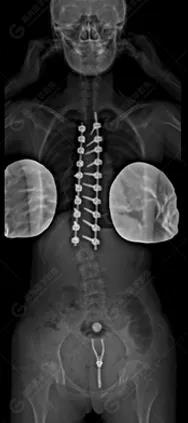

15歲女性,發(fā)現(xiàn)特發(fā)性脊柱側(cè)彎3年,于2019年1月23日來到廣東高尚醫(yī)學(xué)影像診斷中心行EOS檢查,2019年2月行手術(shù)治療后多次到中心行EOS復(fù)查。

2019-07-04

本例患者胸椎右側(cè)彎,Cobb角(T6/T12)為47°,遂行手術(shù)矯正治療。術(shù)后多次隨訪的Cobb角(T10/L3)為12°-15°之間,較術(shù)前明顯縮小。